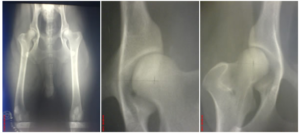

• Gelenkschirurgie

Auch hier sind wir bestrebt mittels bewährter, minimal-invasiver Methoden das Gelenk dauerhaft zu stabilisieren

• ob nach Kreuzbandrissen

• nach Autounfällen mit herausgerissenem Oberschenkel

• offenem Gelenk

• nach eitrigen Entzündungen